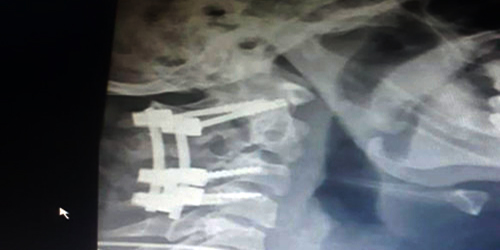

وقد تم تثبيت الكسر بواسطة مسامير وأعمدة وعمل التحام للفقرات العنقية العليا والمتعارف عليه عالميًا بأنه أفضل الطرق الجراحية لمثل هذا النوع من الإصابات وتمت العملية بنجاح تام وغادر المريض المستشفى مترجلاً معافى بفضل الله بعد يومين فقط من الجراحة، ثم بفضل كفاءة الكادر الطبي في المستشفى.